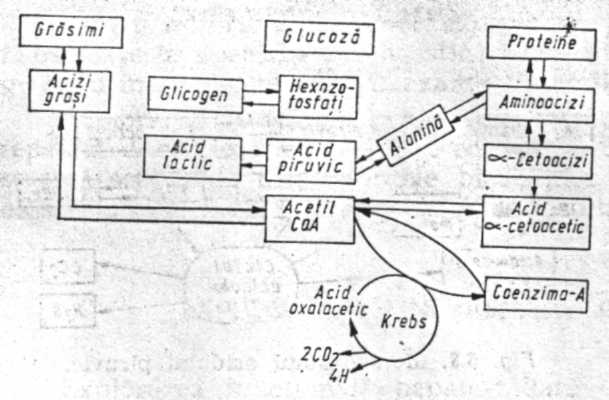

Explorarea functionala hepatobiliara

Explorarea functionala hepatobiliara Explorarea functionala hepatobiliara are in vedere particularitatile anatomice si functionale ale ficatului, metabolice, antitoxice (depozitare, biligenCiteste tot ... 1358 cuvinte

Dimensiune mica

+ cu imagini |